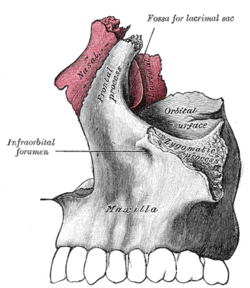

Lateral wall of nasal cavity, showing ethmoid bone in position. Articulation of nasal and lacrimal bones with maxilla.

Articulation of nasal and lacrimal bones with maxilla. Right nasal bone. Outer surface.

Right nasal bone. Outer surface. Right nasal bone. Inner surface.